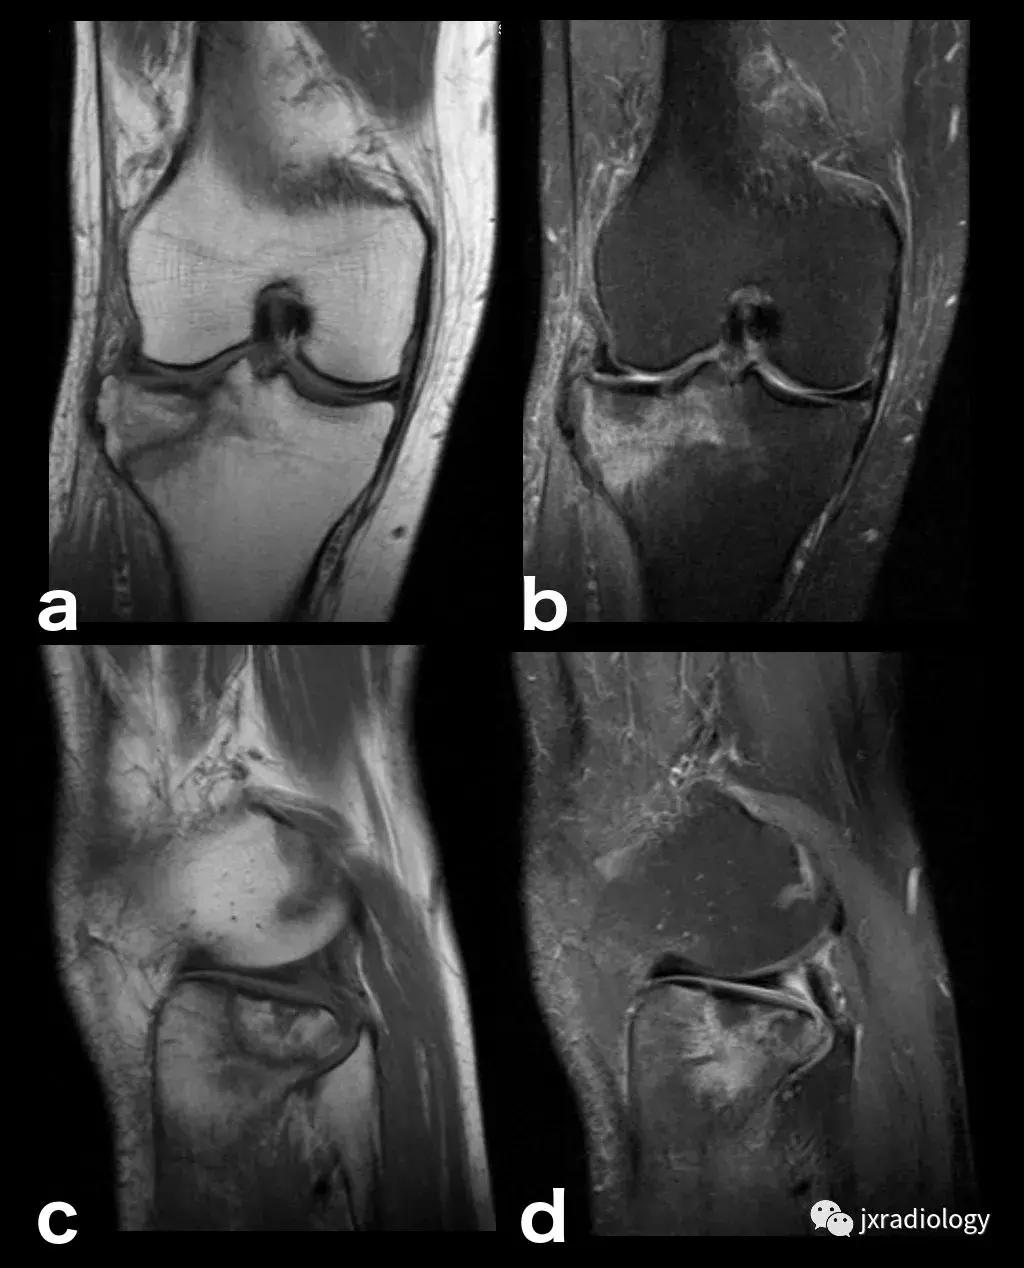

图2:骨性关节炎(OA):男,58岁,股骨内侧髁负重区有软骨缺损,伴有边缘小骨赘和继发性软骨下骨髓水肿。骨性关节炎通常不与创伤性病因分类,而是作为退行性病变分类(a:冠状T1-WI; b:冠状PDWI-FS; c:矢状PDWI-FS)。

图4:SIF(软骨下不全性骨折):在过去,每当在股骨内侧髁上观察到这种软骨下病变时,它就被标记为膝关节自发性骨坏死(SONK)。现在它被认为是一个不全性骨折。这些不全性骨折通常发生在股骨内侧髁和股骨头,并存在于老年人中(它们与骨质疏松症和生物力学改变相关,如在不稳定的半月板损伤中。与其他应力性骨折类似,低信号的骨折线在水敏性序列(a,b:冠状和矢状PDWI-FS)上被高信号的骨髓水肿包围。

图5:长期的SIF(软骨下不全性骨折)伴股骨外侧髁软骨下塌陷、大面积水肿(不如上图中显示的内侧髁位置常见)。

图6:内侧胫骨平台上不常见的SIF(软骨下不全性骨折)(a,b:矢状和冠状PDWI-FS)。